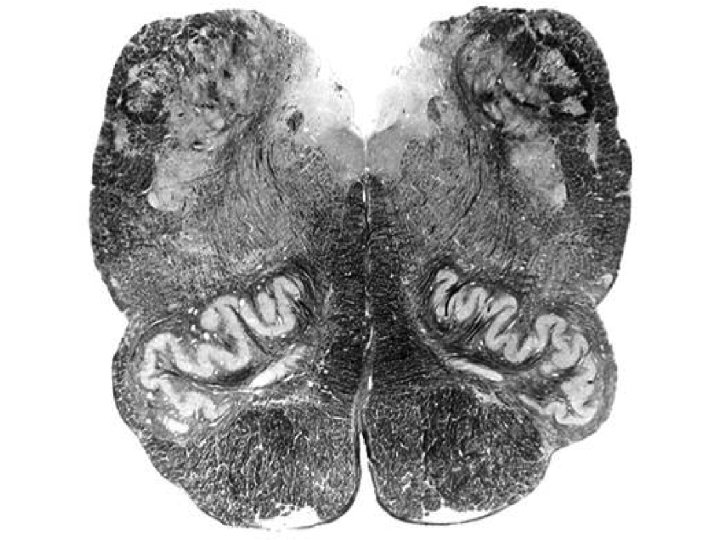

Dentate nucleus

Superior cerebellar peduncle